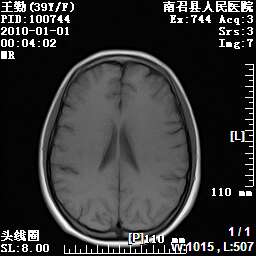

以下是引用随光逐影在2010-1-22 9:03:00的发言:[br]考虑左侧中颅窝(蝶骨翼区)脑膜瘤侵犯蝶骨翼并突入左侧眼眶。

以下是引用水过无痕在2010-1-22 14:55:00的发言:[br]一、定位:颅外占位;二、定性:恶性可能性大;三、组织来源:来源于左侧眼外直肌或其他部位;考虑为:横纹肌肉瘤>转移瘤>脑膜瘤.